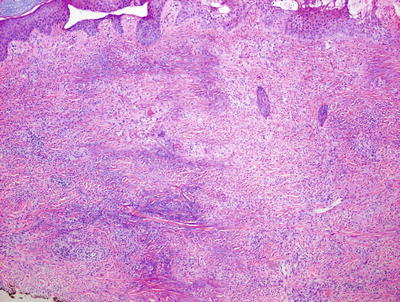

6.3.2 Histology

Skin biopsies from patients with sarcoidosis may demonstrate various histologic patterns. The primary or specific pattern is a granulomatous dermatitis. The histologic features are those of non-caseating granulomas within the dermis (Fig. 6.6). Well-circumscribed clusters of histiocytes are present at throughout the dermis and in the subcutaneous fat, usually without any changes within the epidermis (Fig. 6.7). The presence of granulomas within the papillary dermis, in close proximity to the epidermis is a relatively specific finding. In most cases, only a scant lymphocytic infiltrate is present around the aggregated histiocytes (giving rise to the “naked granulomas” that are described in this entity). Eosinophils and neutrophils are not abundant in sarcoidosis. Foci of caseation are uncommon in sarcoidosis; however, in some cases, granulomas may be interstitial as opposed to tightly aggregated and may demonstrate focal necrosis [17, 18]. Perivascular and peri-adnexal granulomas can be encountered. Peri-adnexal distribution has been described in hereditary early onset sarcoidosis (Blau syndrome ). Foreign bodies can be identified within granulomas in as many as one-third of cases [19].

Fig. 6.6

Sarcoidosis demonstrates multiple small well-formed granulomas with a small number of surrounding lymphocytes within the papillary and reticular dermis

Fig. 6.7

Sarcoidosis is characterized by sharply circumscribed granulomas with relatively little surrounding inflammation